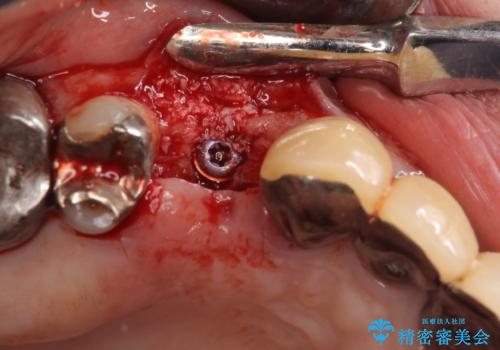

インプラントは、人工骨を用いた際の骨誘導能が比較的高いとさせるストローマン社のSLActiveを使用しました。